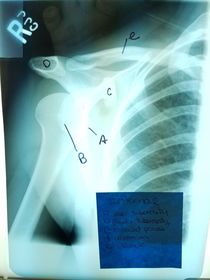

A. acromion B. acromioclavicular joint (AC) C. acromial extremity D. clavicular body E. sternal extremity F. sternoclavicular joint (SC) G. jugular notch H. manubrium of sternum

A. sternoclavicular joint (SC) B. sternal extremity C. body D. acromial extremity E. acromioclavicular joint (AC)

A. acromion B. coracoid process C. inferior angle D. spine of scapula E. body of scapula

A. coracoid process B. glenoid cavity OR scapulohumeral joint C. spine of the scapula D. acromion